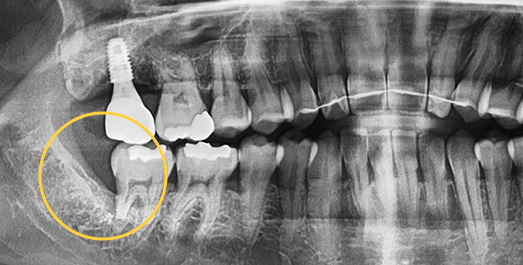

Wisdom tooth extraction by dental specialists

MOHW-certified dental specialists consider the location of adjacent nerves and perform clean, precise extractions even in complex cases.

Even advanced cases

can be extracted.

With extensive experience in numerous advanced cases and a wide range of wisdom tooth extractions, you no longer need to go to a university hospital.